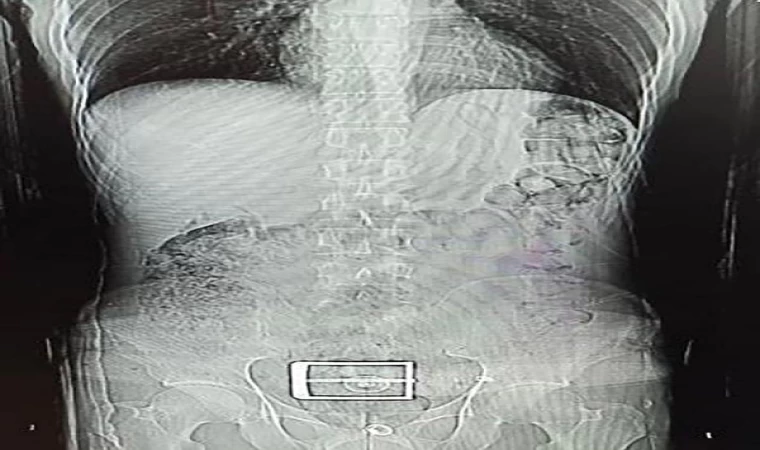

İl Emniyet Müdürlüğü Narkotik Suçlarla Mücadele Şubesi ekipleri, İran uyruklu F.S.'nin (30) durumundan şüphelenip, gözaltına aldı. Şüphelinin, götürüldüğü hastanede çekilen mide ve bağırsak röntgen çekimlerinde, çok sayıda yabancı cisim tespit edildi. Tıbbi müdahaleyle şüphelinin vücudundan 78 kapsül halinde 603,35 gram Afyon sakızı, 17 kapsül halinde 111,35 gram sentetik uyuşturucu çıkarıldı. Şüpheli, emniyetteki işlemlerinin ardından çıkarıldığı hakimlik tarafından tutuklandı. (DHA)

İranlı şüphelinin mide ve bağırsağından uyuşturucu çıktı